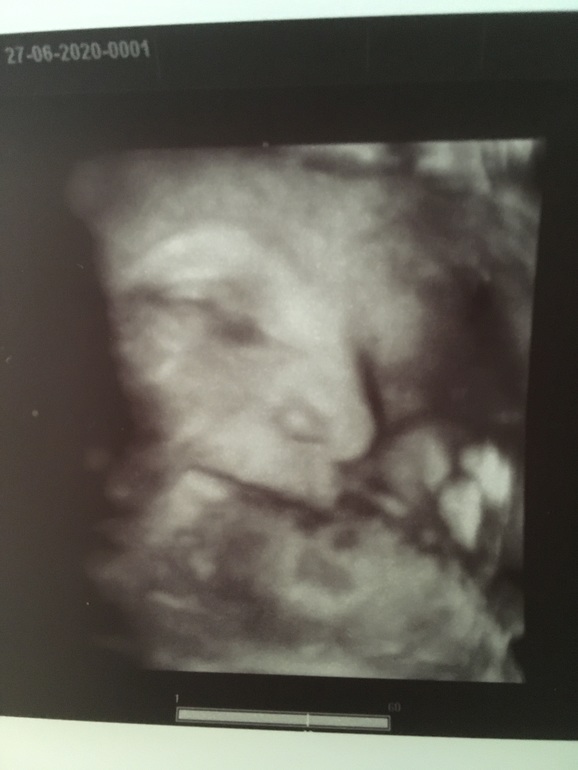

Узи 35 недель и такой большой человек! Фото узи )

Сделала я 3д узи , малыш уже весит 2845 !!! На скрининге в 31,4 он весил 1723грамма )) вот так вот мы вымахали чуть больше чем за 3 недели ) если родимся в срок - думаю будем около 3800 а то и больше ;) пдр сместился с августа на июль ) теперь 31 июля )

Малыш все время отворачивался , открывал рот, высовывал язык )) пару раз улыбнулся и строил хитрые гримасы )) одна из них на фото ;)